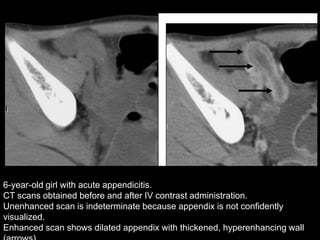

6-year-old girl with acute appendicitis.

CT scans obtained before and after IV contrast administration.

Unenhanced scan is indeterminate because appendix is not confidently

visualized.

Enhanced scan shows dilated appendix with thickened, hyperenhancing wall